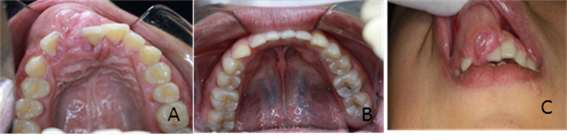

Figura 3. Imágenes Intrabucales

Imagen (a) frente (b) perfil derecho (c) perfil izquierdo.

Figura 4.  Intrabucales Imágenes.

Imagen (a) Oclusal superior (b) oclusal inferior (c) perfil oclusal

Las fotografías intrabucales son de gran ayuda para el diagnóstico de patologías en los pacientes, son una herramienta útil y adicional que aporta información valiosa para el profesional de la odontología, aporta registros clínicos, en este caso la cirugía bucal.